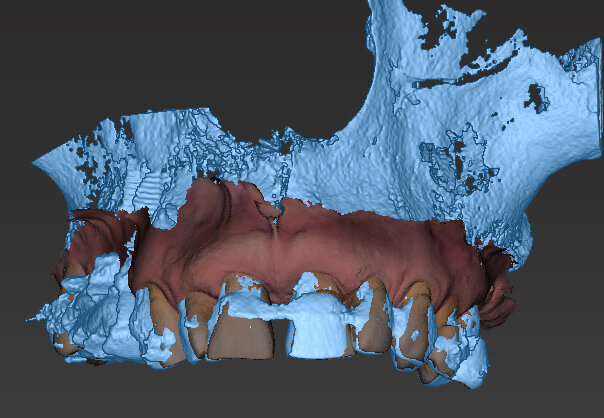

All’esame clinico presenta i quattro incisivi superiori malposizionati, con diastema per evidenti problemi parodontali. Perdita importante di supporto parodontale, presenza di tasche superiori a 6 mm, mobilità di tipo 2/3 su tutti i quattro elementi (Figg. 1-4).

Il piano di trattamento prevede l’estrazione degli elementi dentali, l’inserimento di due impianti e la realizzazione di una protesi fissa di quattro elementi. Il problema da gestire è quello della fase provvisoria. Non è ipotizzabile una protesi mobile e quindi programmiamo di inserire subito dopo l’intervento un provvisorio immediato. Questo ci consente di condizionare da subito i tessuti periimplantari e anche le zone dei ponti. Si rileva un’impronta digitale (Figg. 5, 6), e la programmazione degli impianti viene effettuata con un software di chirurgia guidata (Fig. 7) e la posizione degli impianti nello spazio biologico e nello spazio protesico viene fatta sulla base di una ceratura diagnostica (Figg. 8, 9). Inseriamo gli impianti virtuali nell’osso disponibile (Figg. 10-13) e in relazione all’aspetto protesico correggiamo l’asse di inclinazione degli impianti con componenti secondarie angolate a 17° (Figg. 14, 15). Questo ci consentirà di realizzare una protesi avvitata con i fori situati nella zona palatale.

Fig. 5 - Impronta iniziale digitale.

Fig. 6 - Visione occlusale.